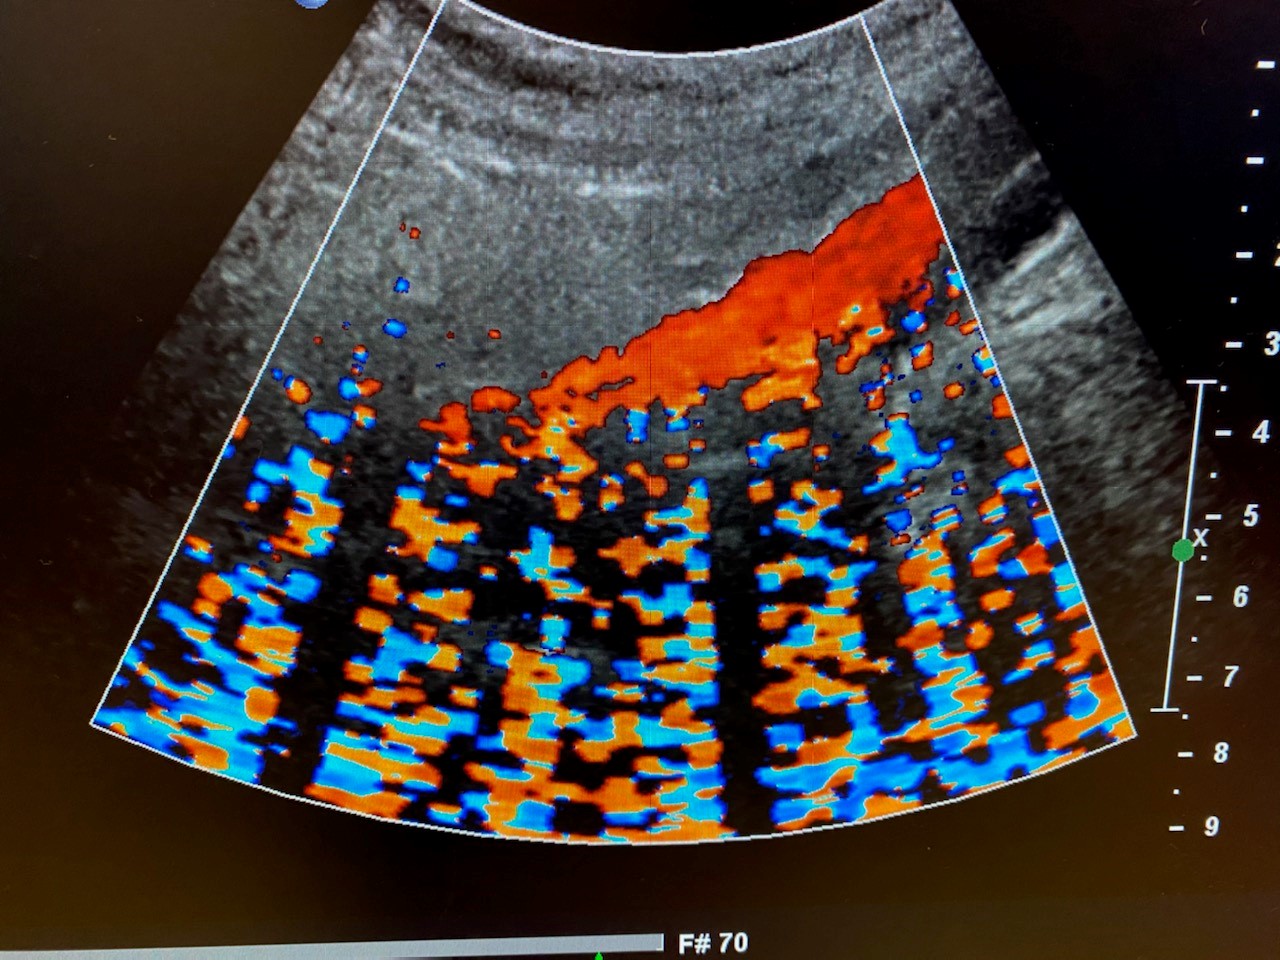

From ecgwaves.com

Artifacts in ultrasound imaging Cardiovascular Education How To Reduce Acoustic Noise Ultrasound Thus, it is possible to improve the quality of kidney ultrasound image by reducing the speckle noise and enhancing the boundary by implementation of automatic segmentation method using the. Usually, medical ultrasound images are affected by the mixed noise, which is the combination of speckle noise and gaussian. To reduce speckle noise, ultrasound compounding techniques have been widely investigated. To. How To Reduce Acoustic Noise Ultrasound.